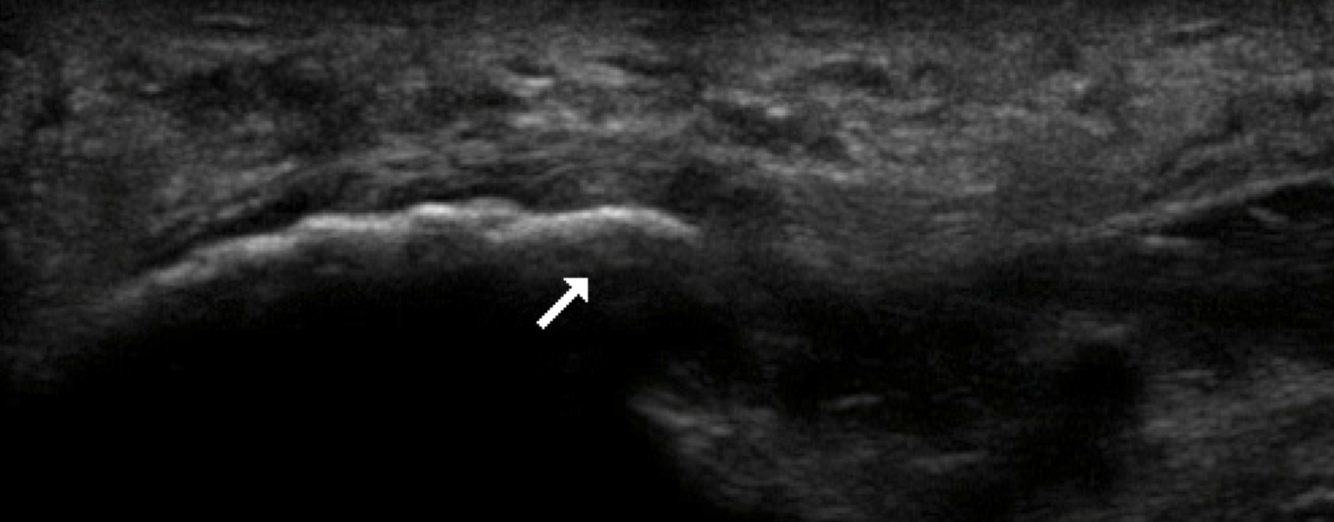

Q

Quoi la pathologie ici?

A

Kyste ganglionnaire intra-neural (où il y a des petites étoiles